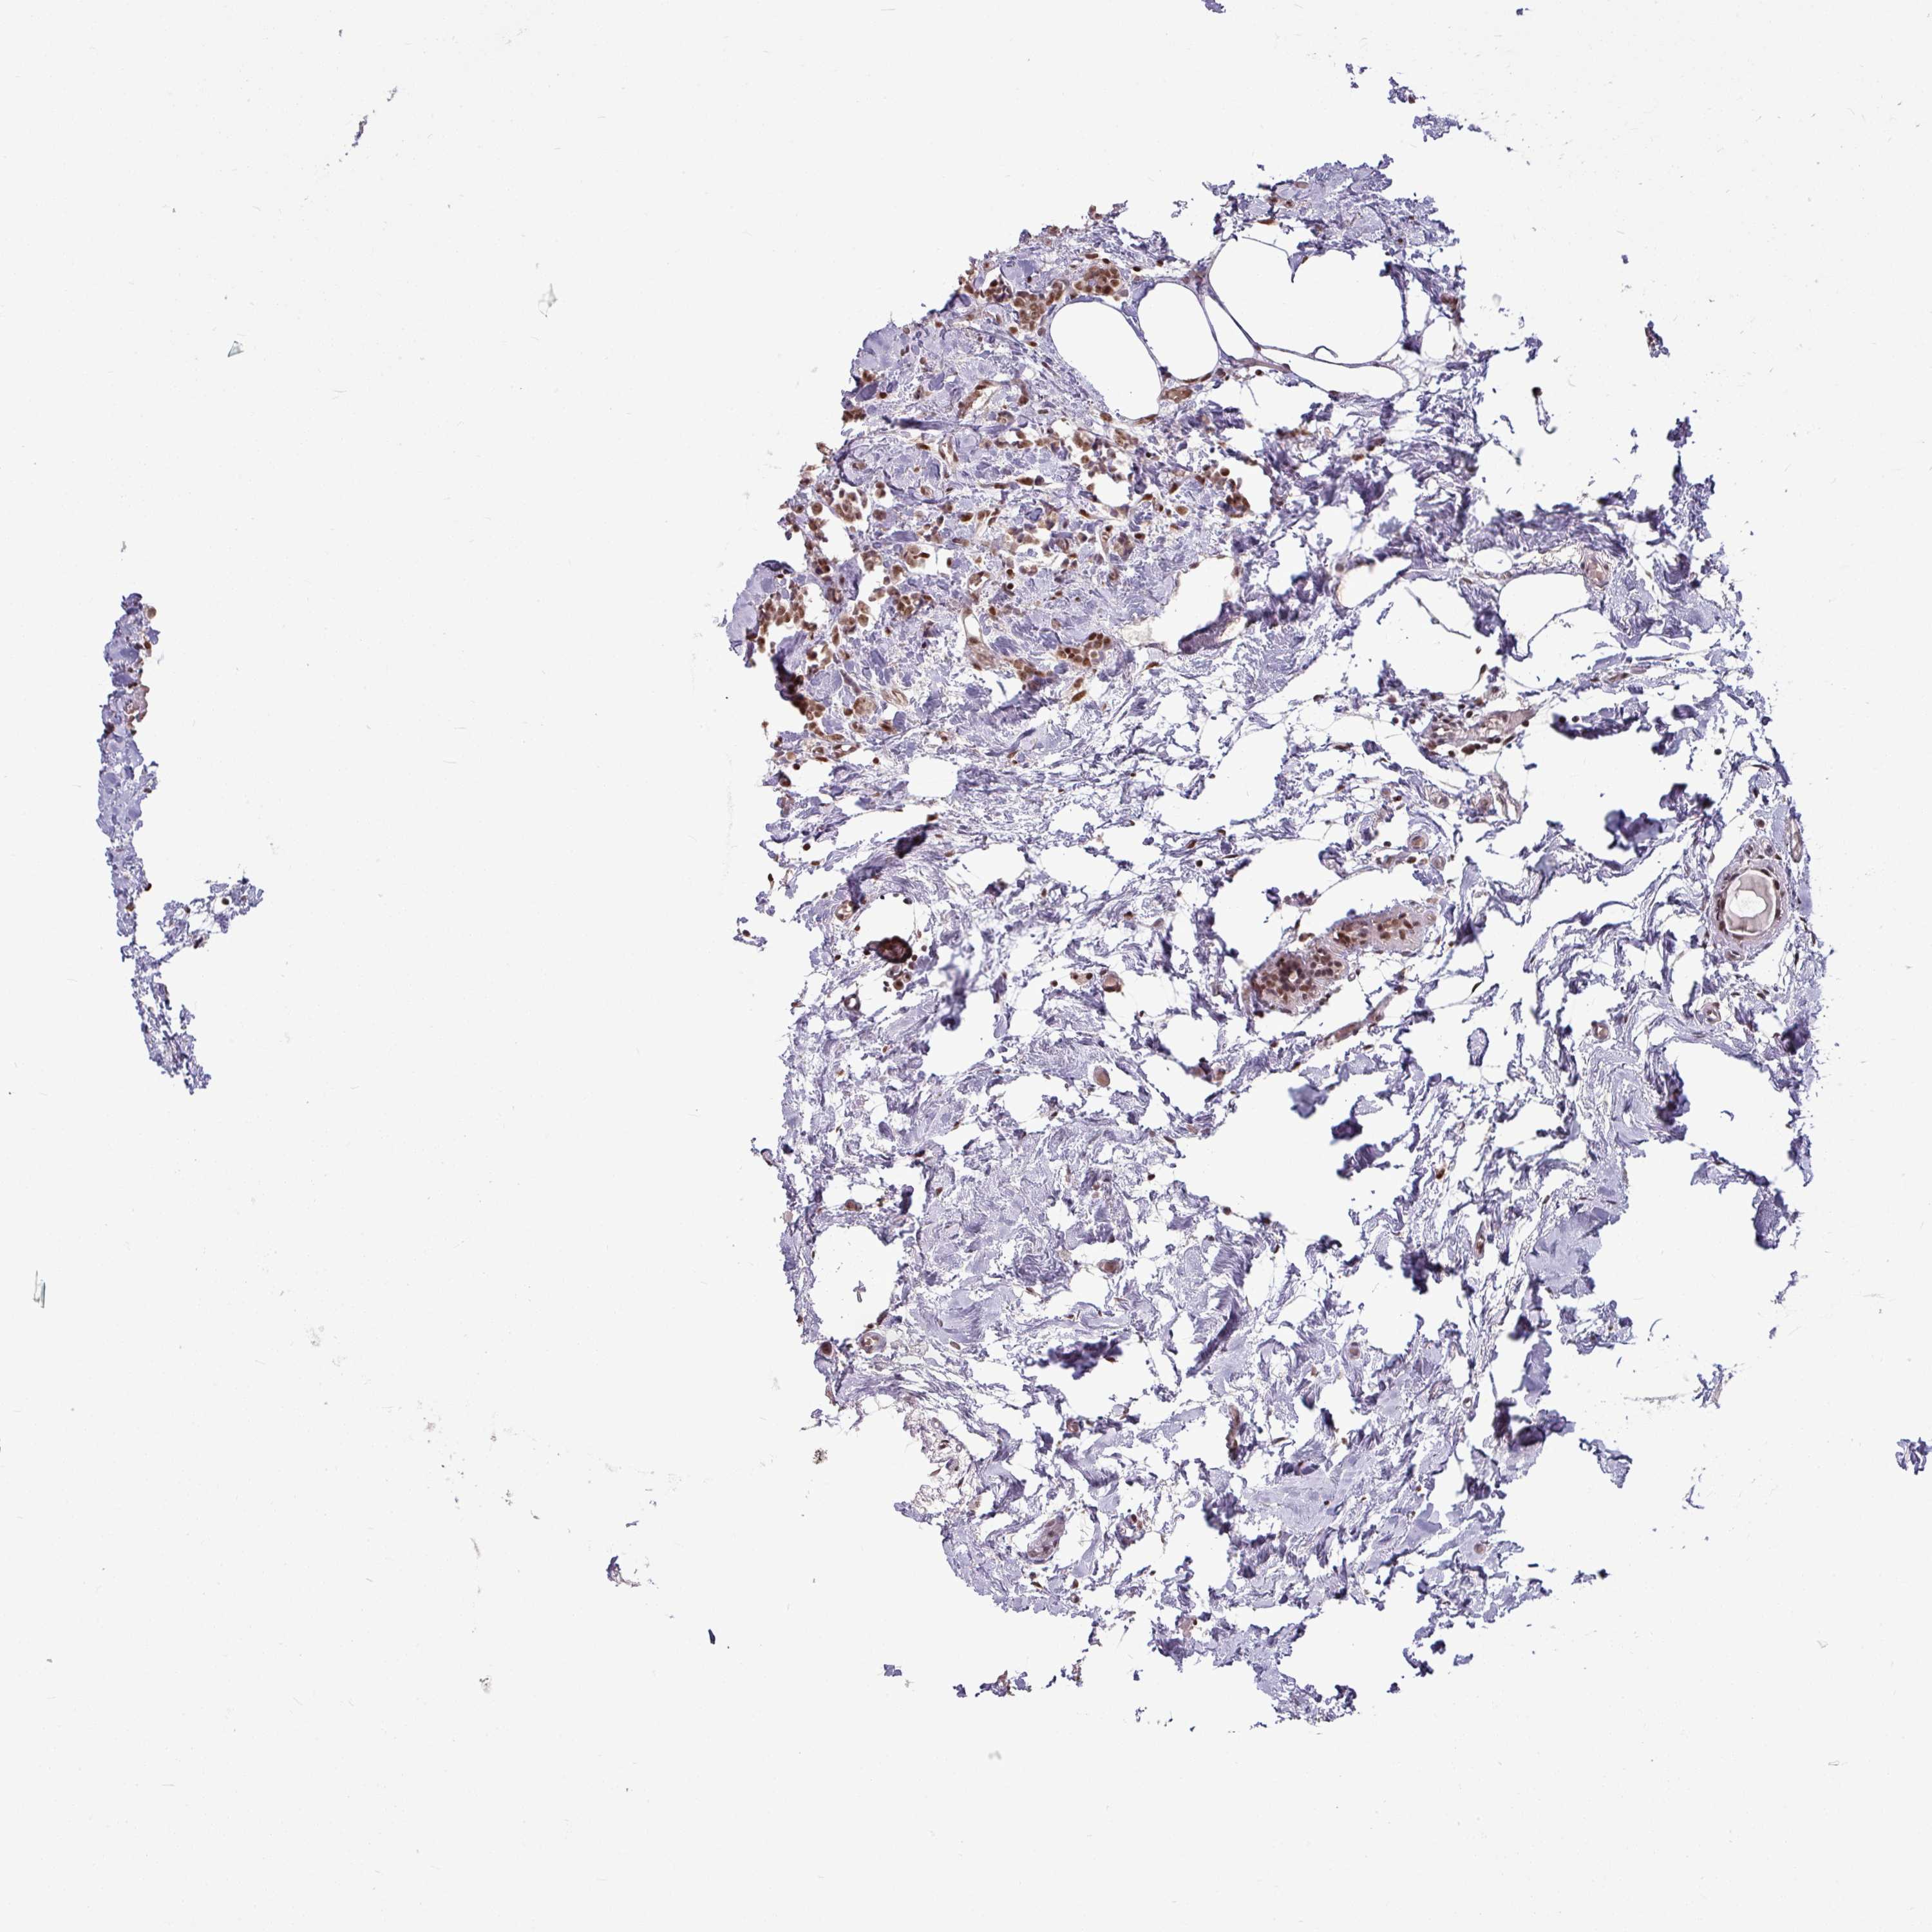

CANCER BREAST CANCER Show tissue menu

BRCA TCGA BRCA VALIDATION PROTEIN EXPRESSION